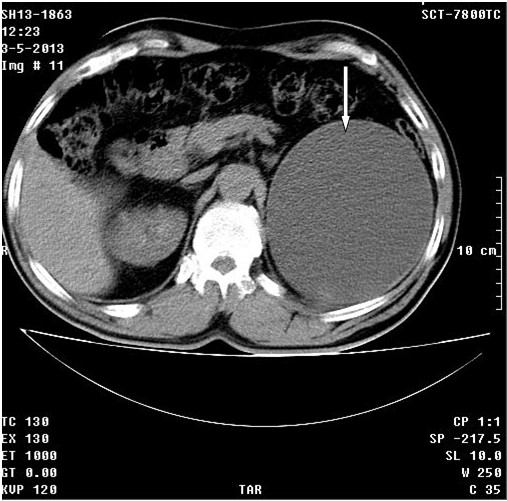

Se realizó tomografía axial computadorizada simple y TAC simple y tomografía con contraste endovenoso y con vistas tardías. Se observó el riñón derecho con dilatación moderada del sistema excretor con posibilidad de quiste asociado (Flecha fina). En el riñón izquierdo se observó proceso expansivo de baja densidad de 13 cm con gruesa cápsula hacia la porción superior del mismo con componente quístico asociado, que provoca retardo en la eliminación del contraste por este lado. (Figuras 1 A, B, C, D flechas gruesas)

Tumor en riñón izquierdo, carcinoma papilar acinoso de 10 cm de células renales. Al paciente se le realizó una cirugía polar de RI, evolucionó satisfactoriamente.

En UTS de seguimiento se observó que el RI mide 95x49, parénquima de 13 mm, conservado; el derecho mide 119x65mm, parénquima de 13 mm, con tres imágenes quísticas, la mayor calicial de 30 mm, sin repercusión, vejiga vacía.